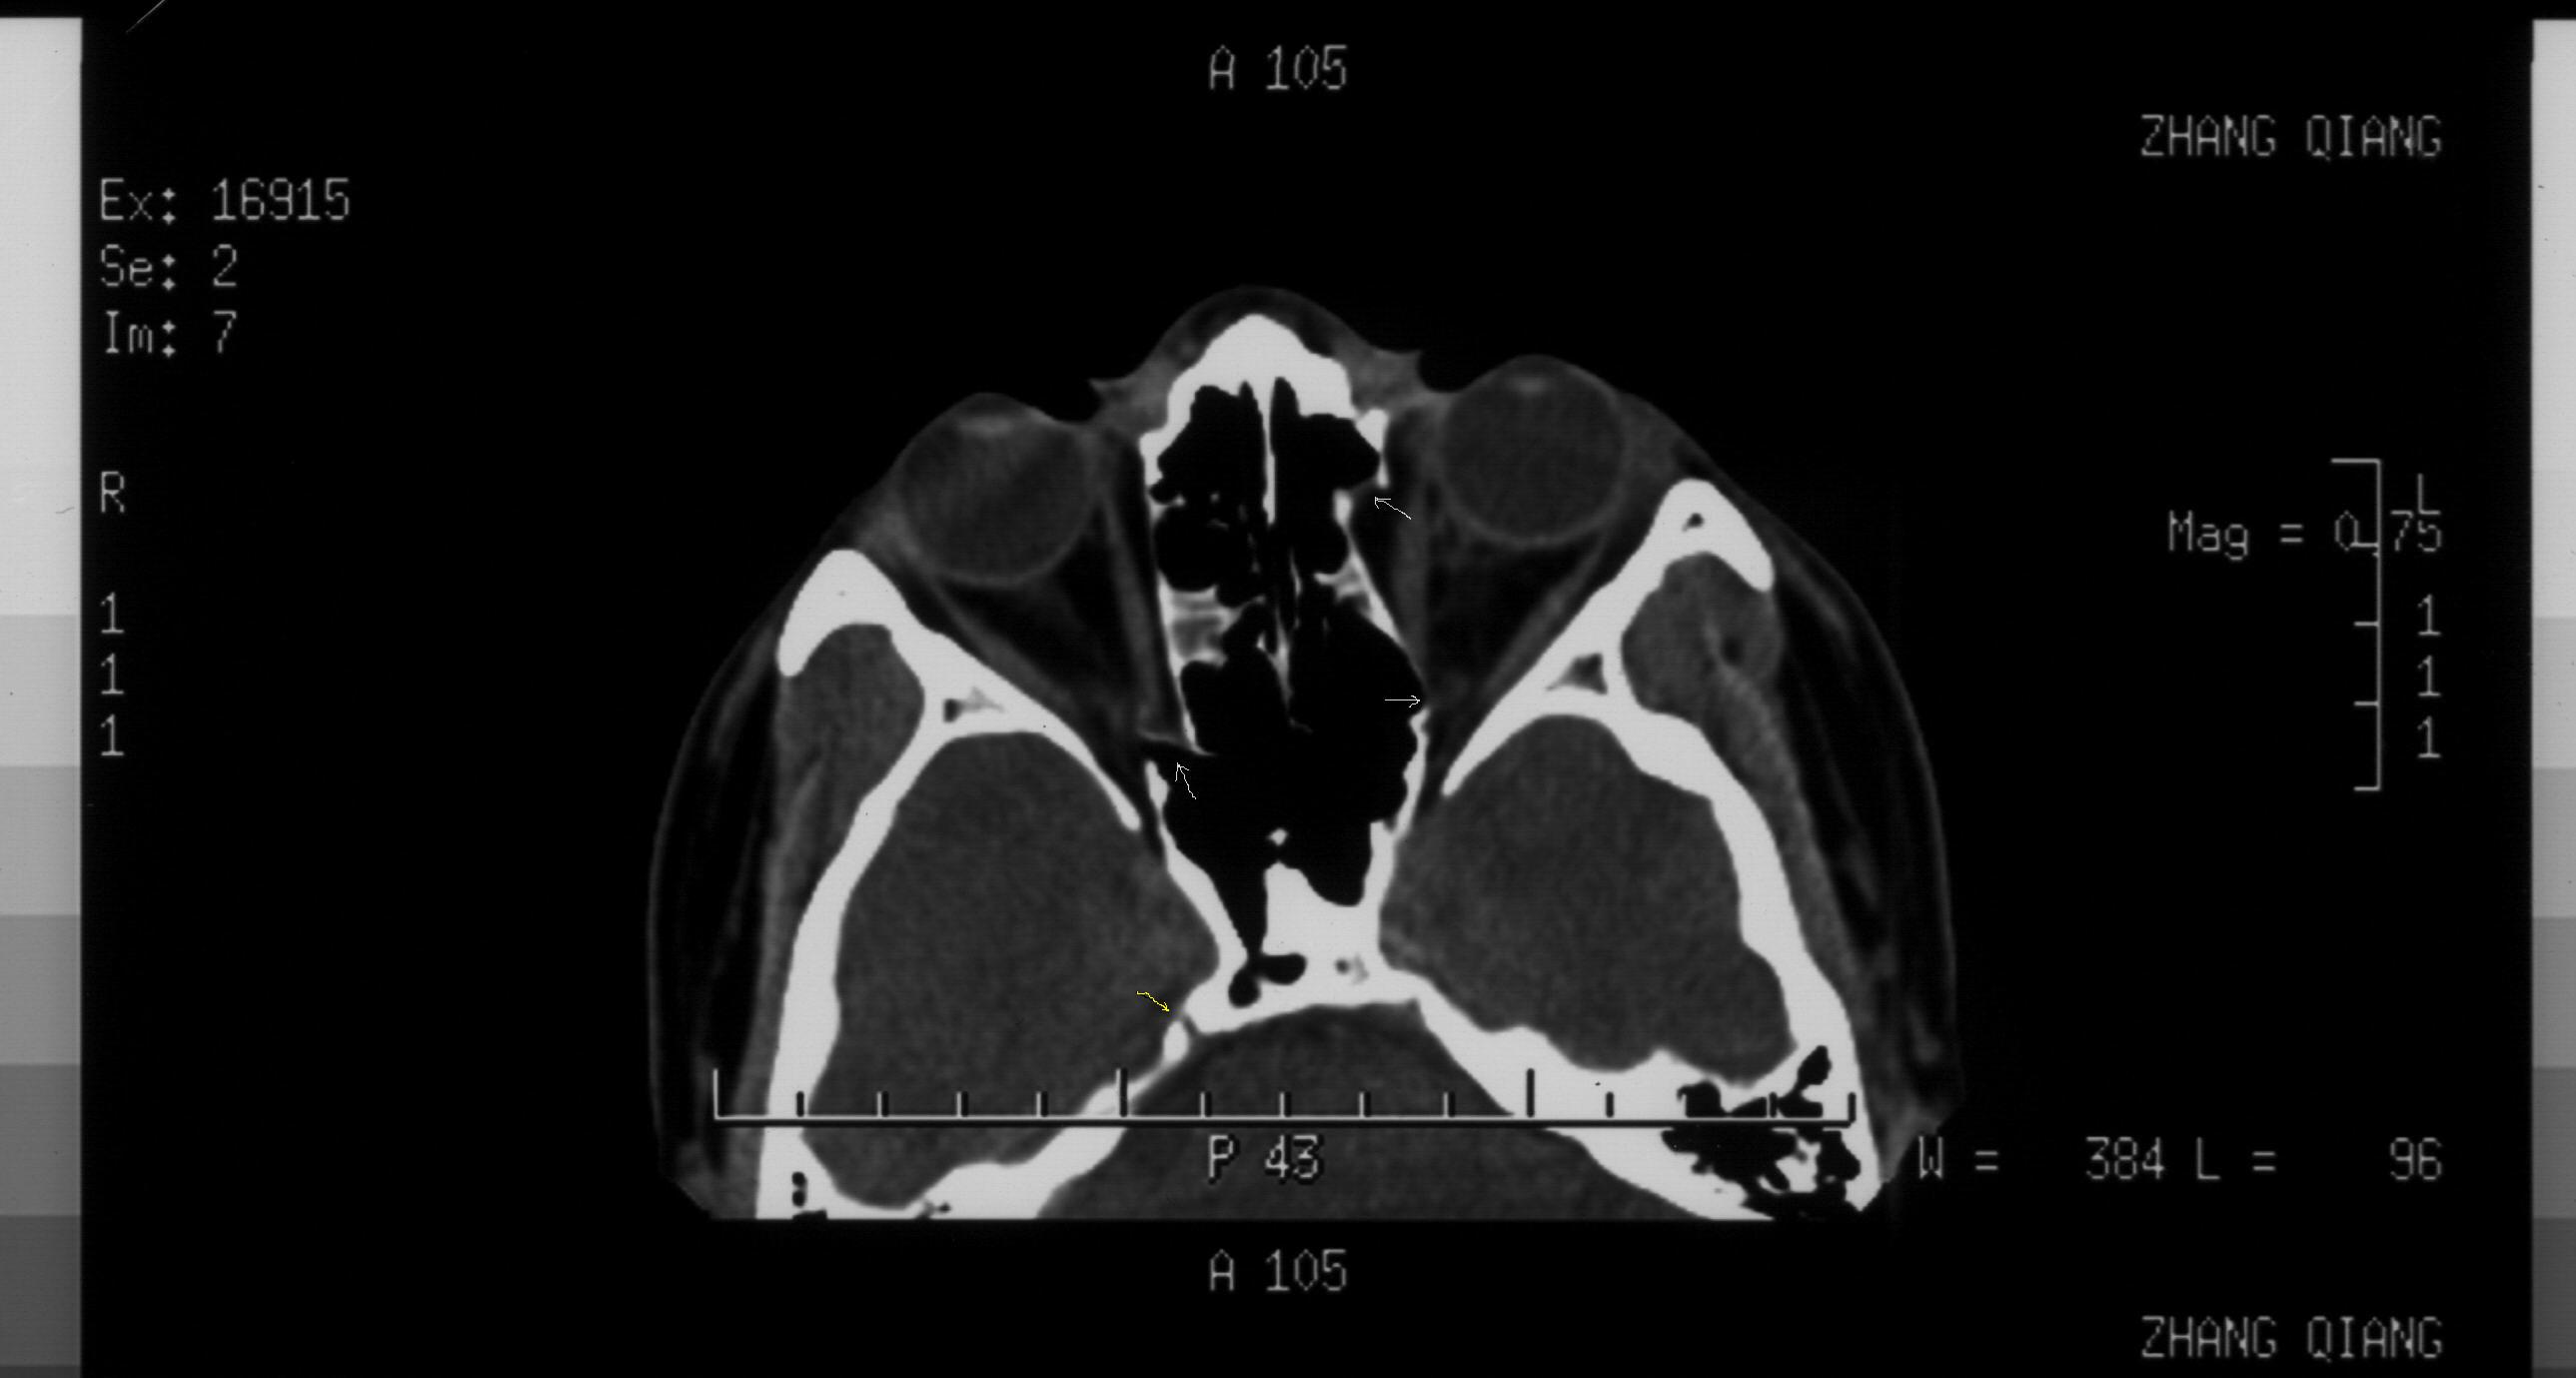

双眼拳击伤 双眼全方位复视

请解读一下ct片

图588:可以看到箭头所示双侧纸样板骨折、移位。右侧骨折部位靠近眶尖,需要注意以下问题:1、通过视神经管薄层扫描除外视神经管骨折(结合临床视力和瞳孔反射)2、调出软组织窗,本人高度怀疑有内直肌近腱环处撕裂伤抑或是合并嵌顿。如同所述,则是急诊手术的绝对适应症,不能延误。左侧前部纸样板骨折明确,内直肌并未嵌顿在此处。而后部为可以骨折,希望结合上下层面及临床考虑,处理原则同前述。顺便提一下,右侧岩锥可疑裂缝,虽不能完全除外骨折,不过本人觉得正常骨缝的可能性更大。根据影像学经验,一般颅骨线状骨折的裂缝比较细小。另外,如果该部位出现骨折,则伴随临近部位的组织损伤和功能损害,果真如此,那就麻烦大了:首先,从神经科角度,颞叶出血、水肿或者该处脑膜下积血都会很严重。而此处又比邻海绵窦,可能的情况不用说了。第3、我们知道外展神经是颅内走行最长的颅神经。而在这个部位的解剖特点是边缘锐利,外展神经经此爬行,若发生外伤很容易伤及神经。所以,你要是真的想进一步了解这个区域,建议你行颅底薄扫加MRI。你自己权衡吧。

图560:箭头所示左侧鼻骨及鼻中隔骨折明确。另外,对于眼科医生应同时关注鼻泪管。通常这个部位容易被放射科大夫所忽视。